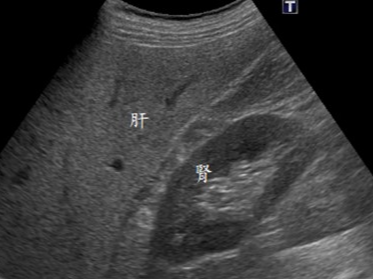

간은 복부 초음파의 핵심 관찰 대상입니다. 간 실질의 에코 패턴을 통해 지방간 여부를 비교적 정확하게 판단할 수 있으며, 지방 침착의 정도에 따라 경증, 중등도, 중증으로 나누어 추정이 가능합니다. 또한 간낭종, 간혈관종과 같은 양성 종양은 초음파에서 특징적인 모양으로 관찰되는 경우가 많아 추적 관찰 여부를 결정하는 데 도움이 됩니다. 간경변이 진행된 경우에는 간 표면이 불규칙해지고 비장이 커지는 소견이 함께 나타날 수 있으며, 이는 만성 간질환의 중요한 단서가 됩니다. 다만 간암의 경우 초기 병변은 초음파에서 놓칠 수 있어, 고위험군에서는 CT나 MRI와 병행하는 것이 일반적입니다.